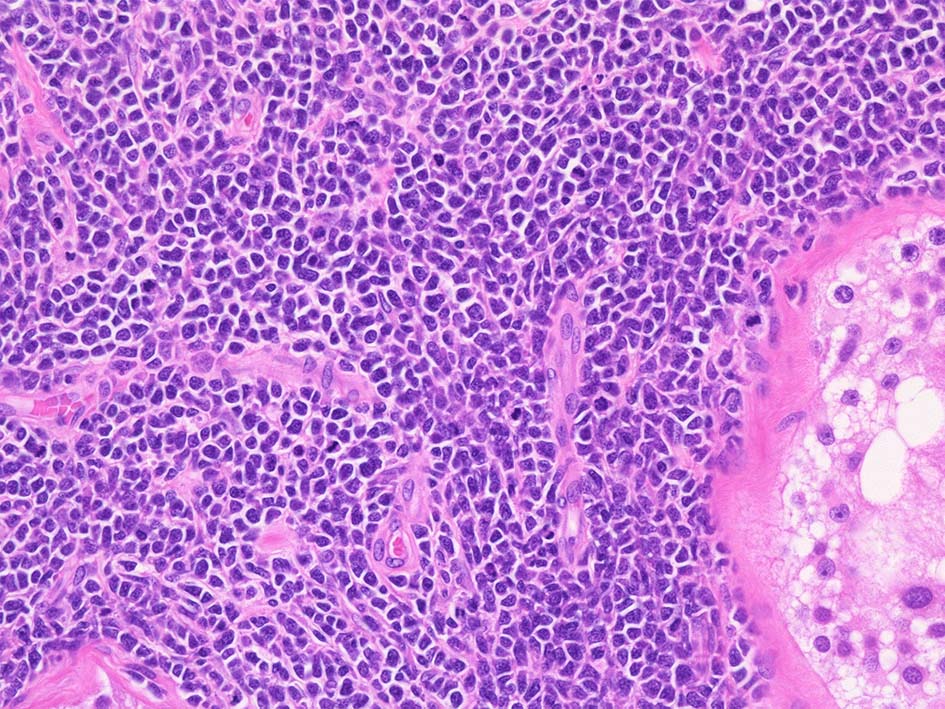

精細管は浸潤により萎縮, 消失. びまん性にcentroblasts/immunoblastsの増殖が認められる. 腫瘍細胞間に軽度の線維化がある.

小リンパ球と同程度か1.5倍くらいのサイズ, round/ convoluted nucleiをもつリンパ球がシート状密に増殖する. 核クロマチンは粗で, 核小体が認められる核もある.

DLBCLとは細胞の大きさや細胞所見が異なっている. 精細管への浸潤, 占拠所見がある.